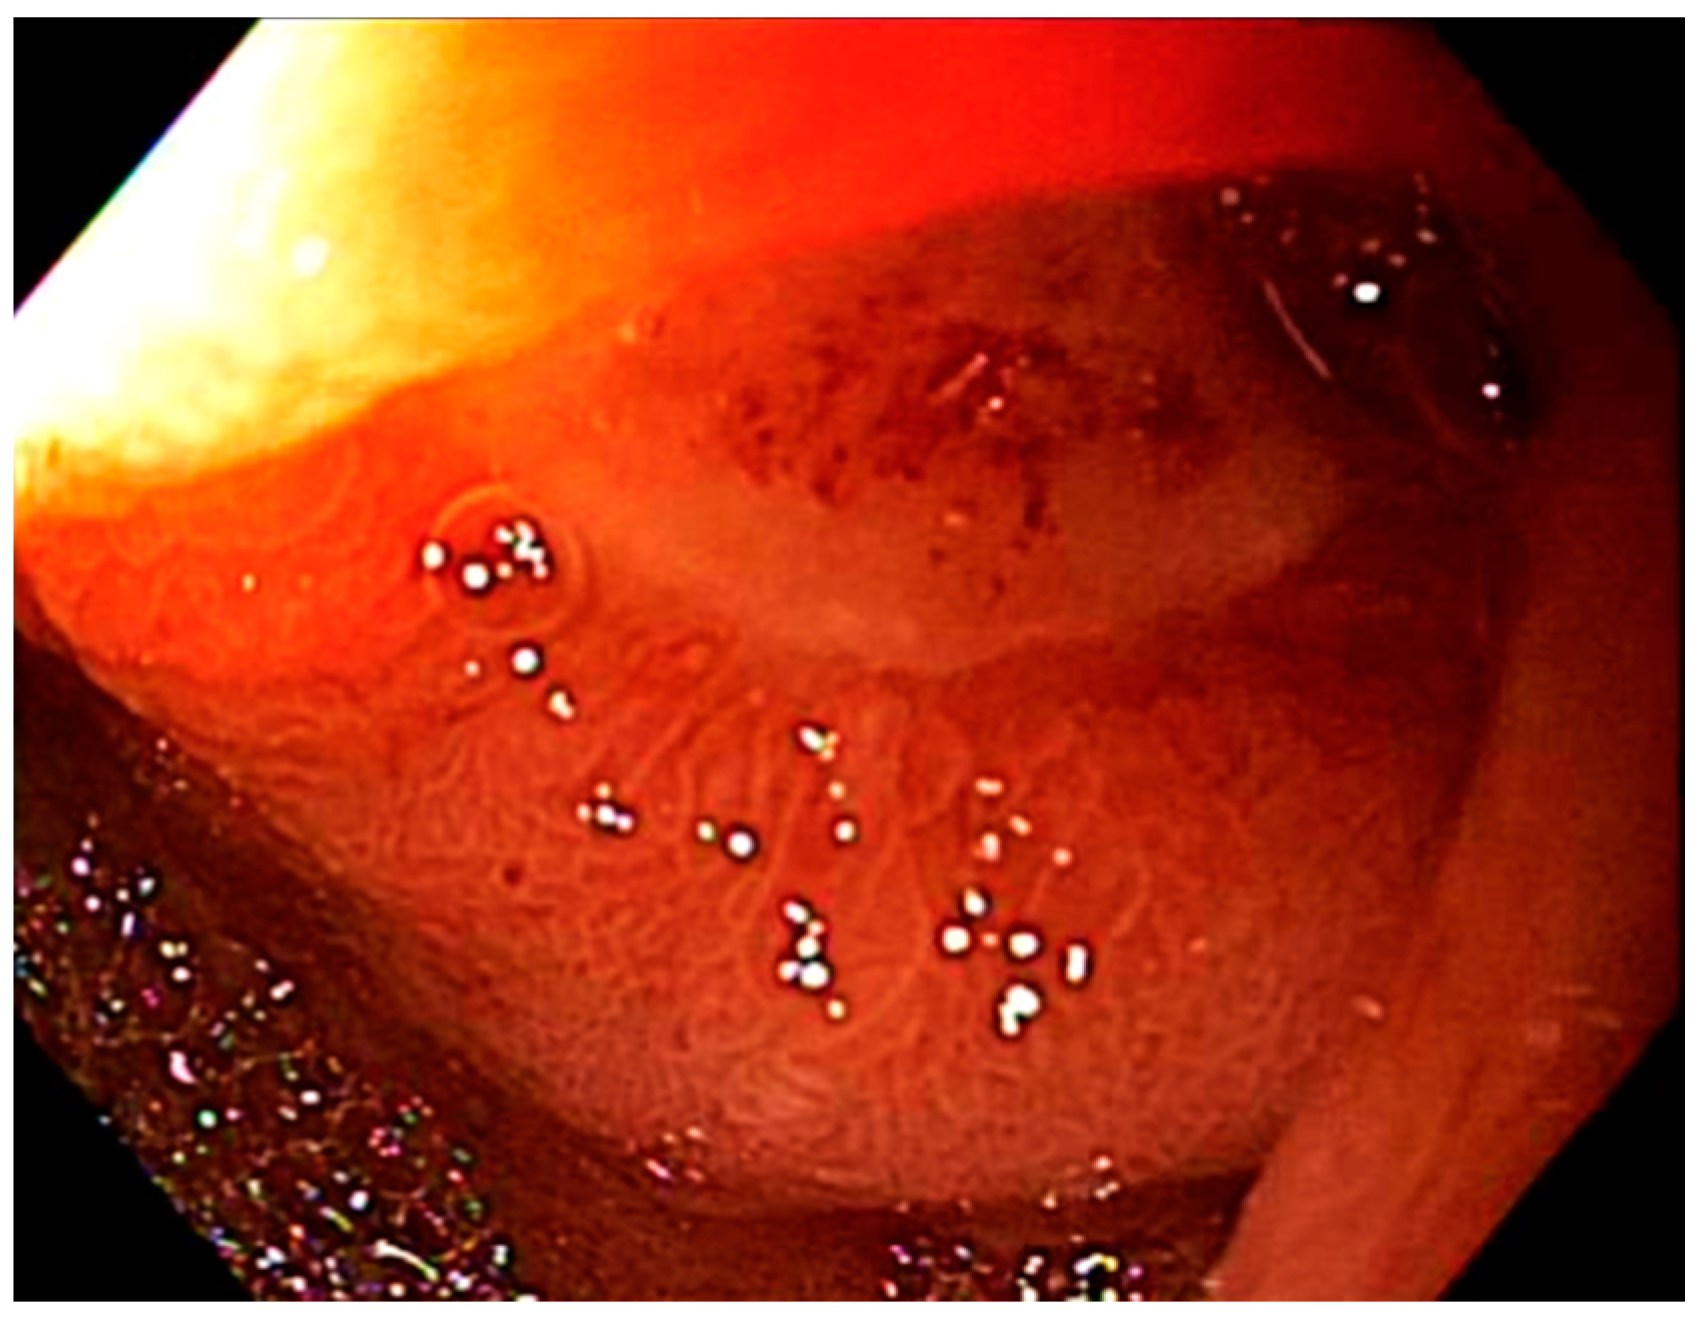

4.3. Toxicity Scoring System

| Erythema | 0 = none 1 = mild (pink) 2 = moderate/severe (red) | ||

| Edema | 0 = none 1 = mild 2 = moderate/severe | ||

| Ulcers * | 0 = none 1 = single 2 = 2 or more ulcers | ||

| Stricture | 0 = none 1 = mild 2 = moderate/severe | ||

| Total Score: | Total Score: 0 = None 1–2 = Mild toxicity 3–4 = Moderate toxicity ≥5 = Severe toxicity | ||